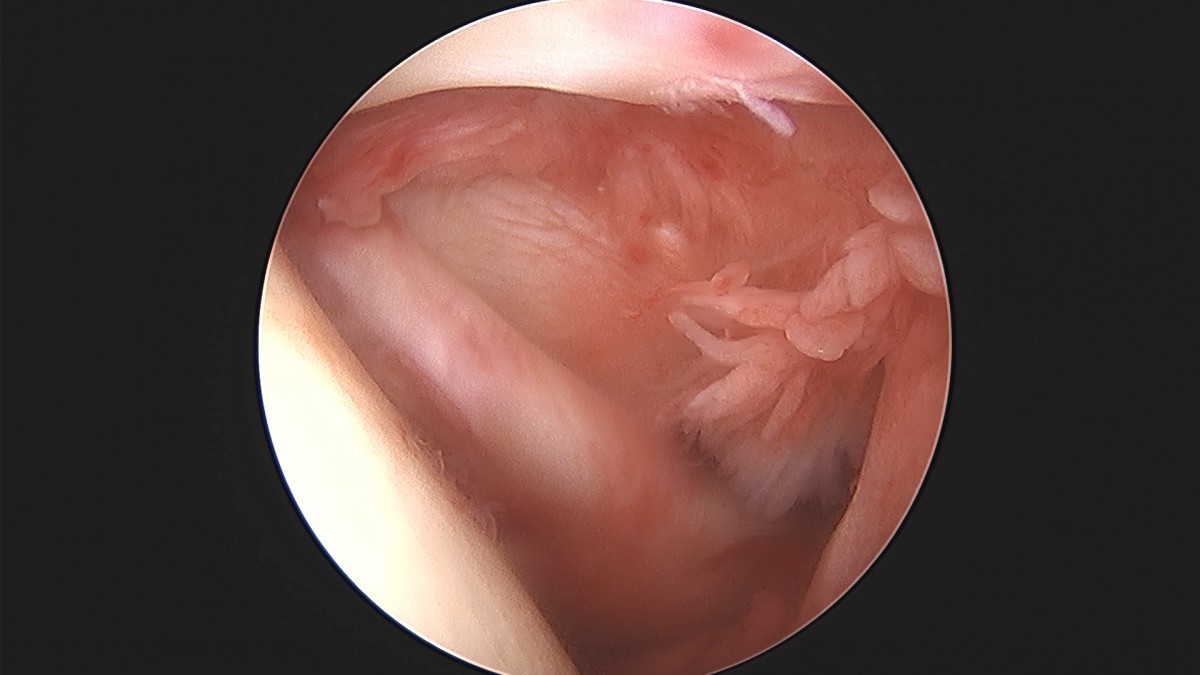

이재상원장님 어깨 견봉하 감압술 및 관절낭 이완술 박창O 환자

dae765e4d9ac96aee867c9d6292d8784_1758004610_4344.jpg